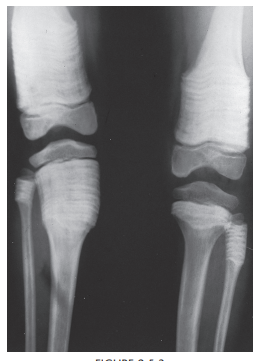

Mulitple Hereditary exostosis

Multiple hereditary exostosis